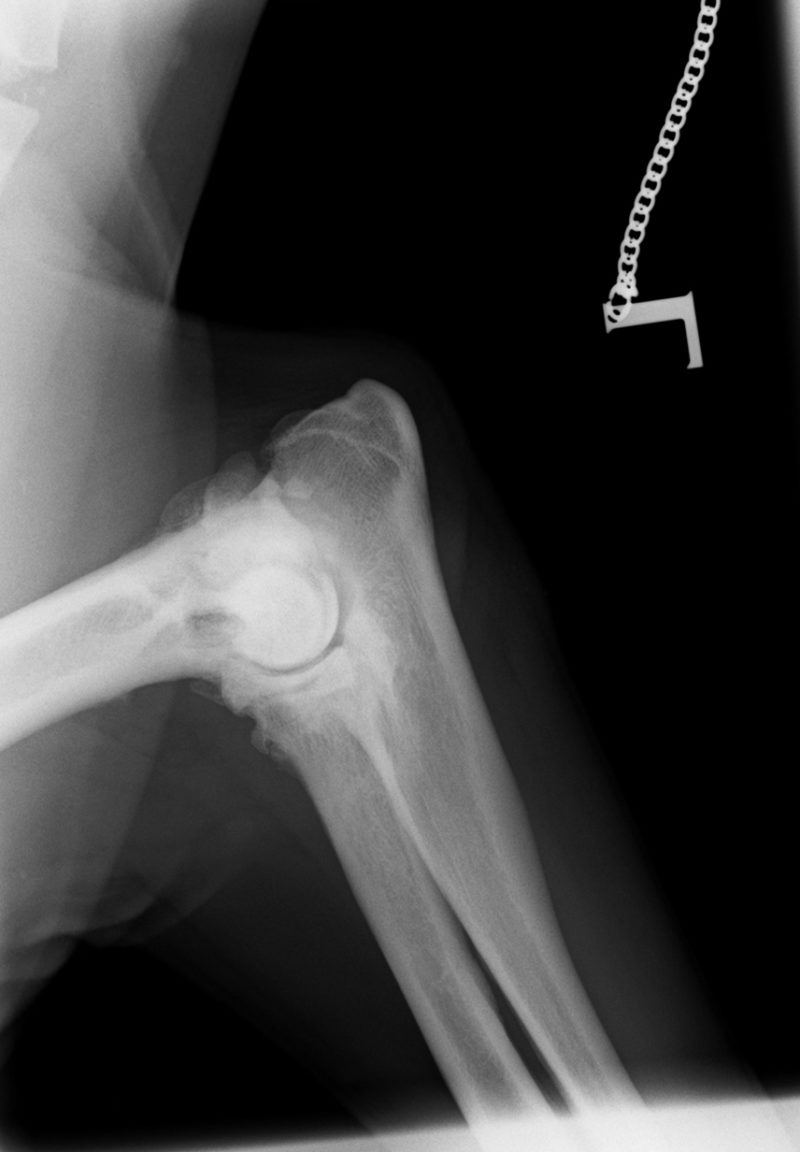

Ellenbogengelenksarthrose bei Labrador ...

Im August 2013 wurde ein acht Jahre alter männlich kastrierter Labrador mit beidseitig hochgradiger  Ellenbogengelenksarthrose vorgestellt. Der Hund war beidseits wegen eines frakturierten Processus Coronoideus (Der Proccesus Coronoideus stellt einen wichtigen knöchernen Stabilisator des Ellenbogengelenks dar) operiert, einseitig nachoperiert und auf beiden Seiten mehrfach mit Cortison-Injektionen behandelt worden.